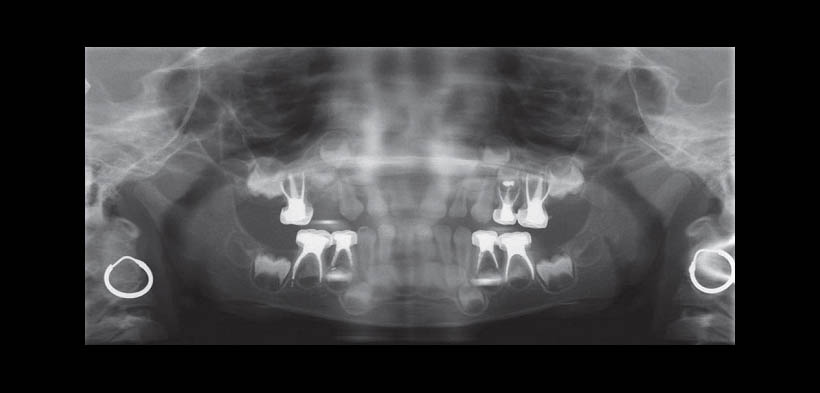

Fig. 1. Radiografía panorámica preoperatoria que muestra caries con compromiso pulpar de todos los molares primarios con reabsorción radicular de la pieza 54.

Fig. 2. Radiografía panorámica: una semana postoperatoria mostrando el material de obturación de conducto (Diapex®) en las piezas 6.4, 7.4, 8.4 y 8.5.